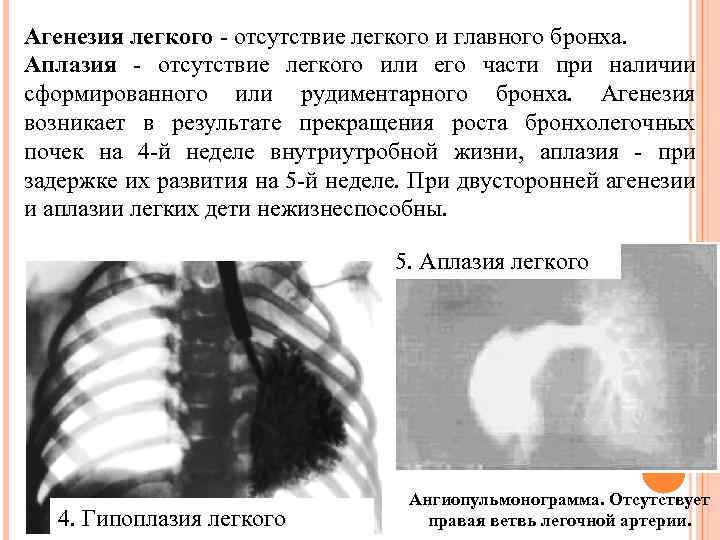

Агенезия легкого - отсутствие легкого и главного бронха. Аплазия - отсутствие легкого или его части при наличии сформированного или рудиментарного бронха. Агенезия возникает в результате прекращения роста бронхолегочных почек на 4 -й неделе внутриутробной жизни, аплазия - при задержке их развития на 5 -й неделе. При двусторонней агенезии и аплазии легких дети нежизнеспособны. 5. Аплазия легкого 4. Гипоплазия легкого Ангиопульмонограмма. Отсутствует правая ветвь легочной артерии.

Агенезия легкого - отсутствие легкого и главного бронха. Аплазия - отсутствие легкого или его части при наличии сформированного или рудиментарного бронха. Агенезия возникает в результате прекращения роста бронхолегочных почек на 4 -й неделе внутриутробной жизни, аплазия - при задержке их развития на 5 -й неделе. При двусторонней агенезии и аплазии легких дети нежизнеспособны. 5. Аплазия легкого 4. Гипоплазия легкого Ангиопульмонограмма. Отсутствует правая ветвь легочной артерии.